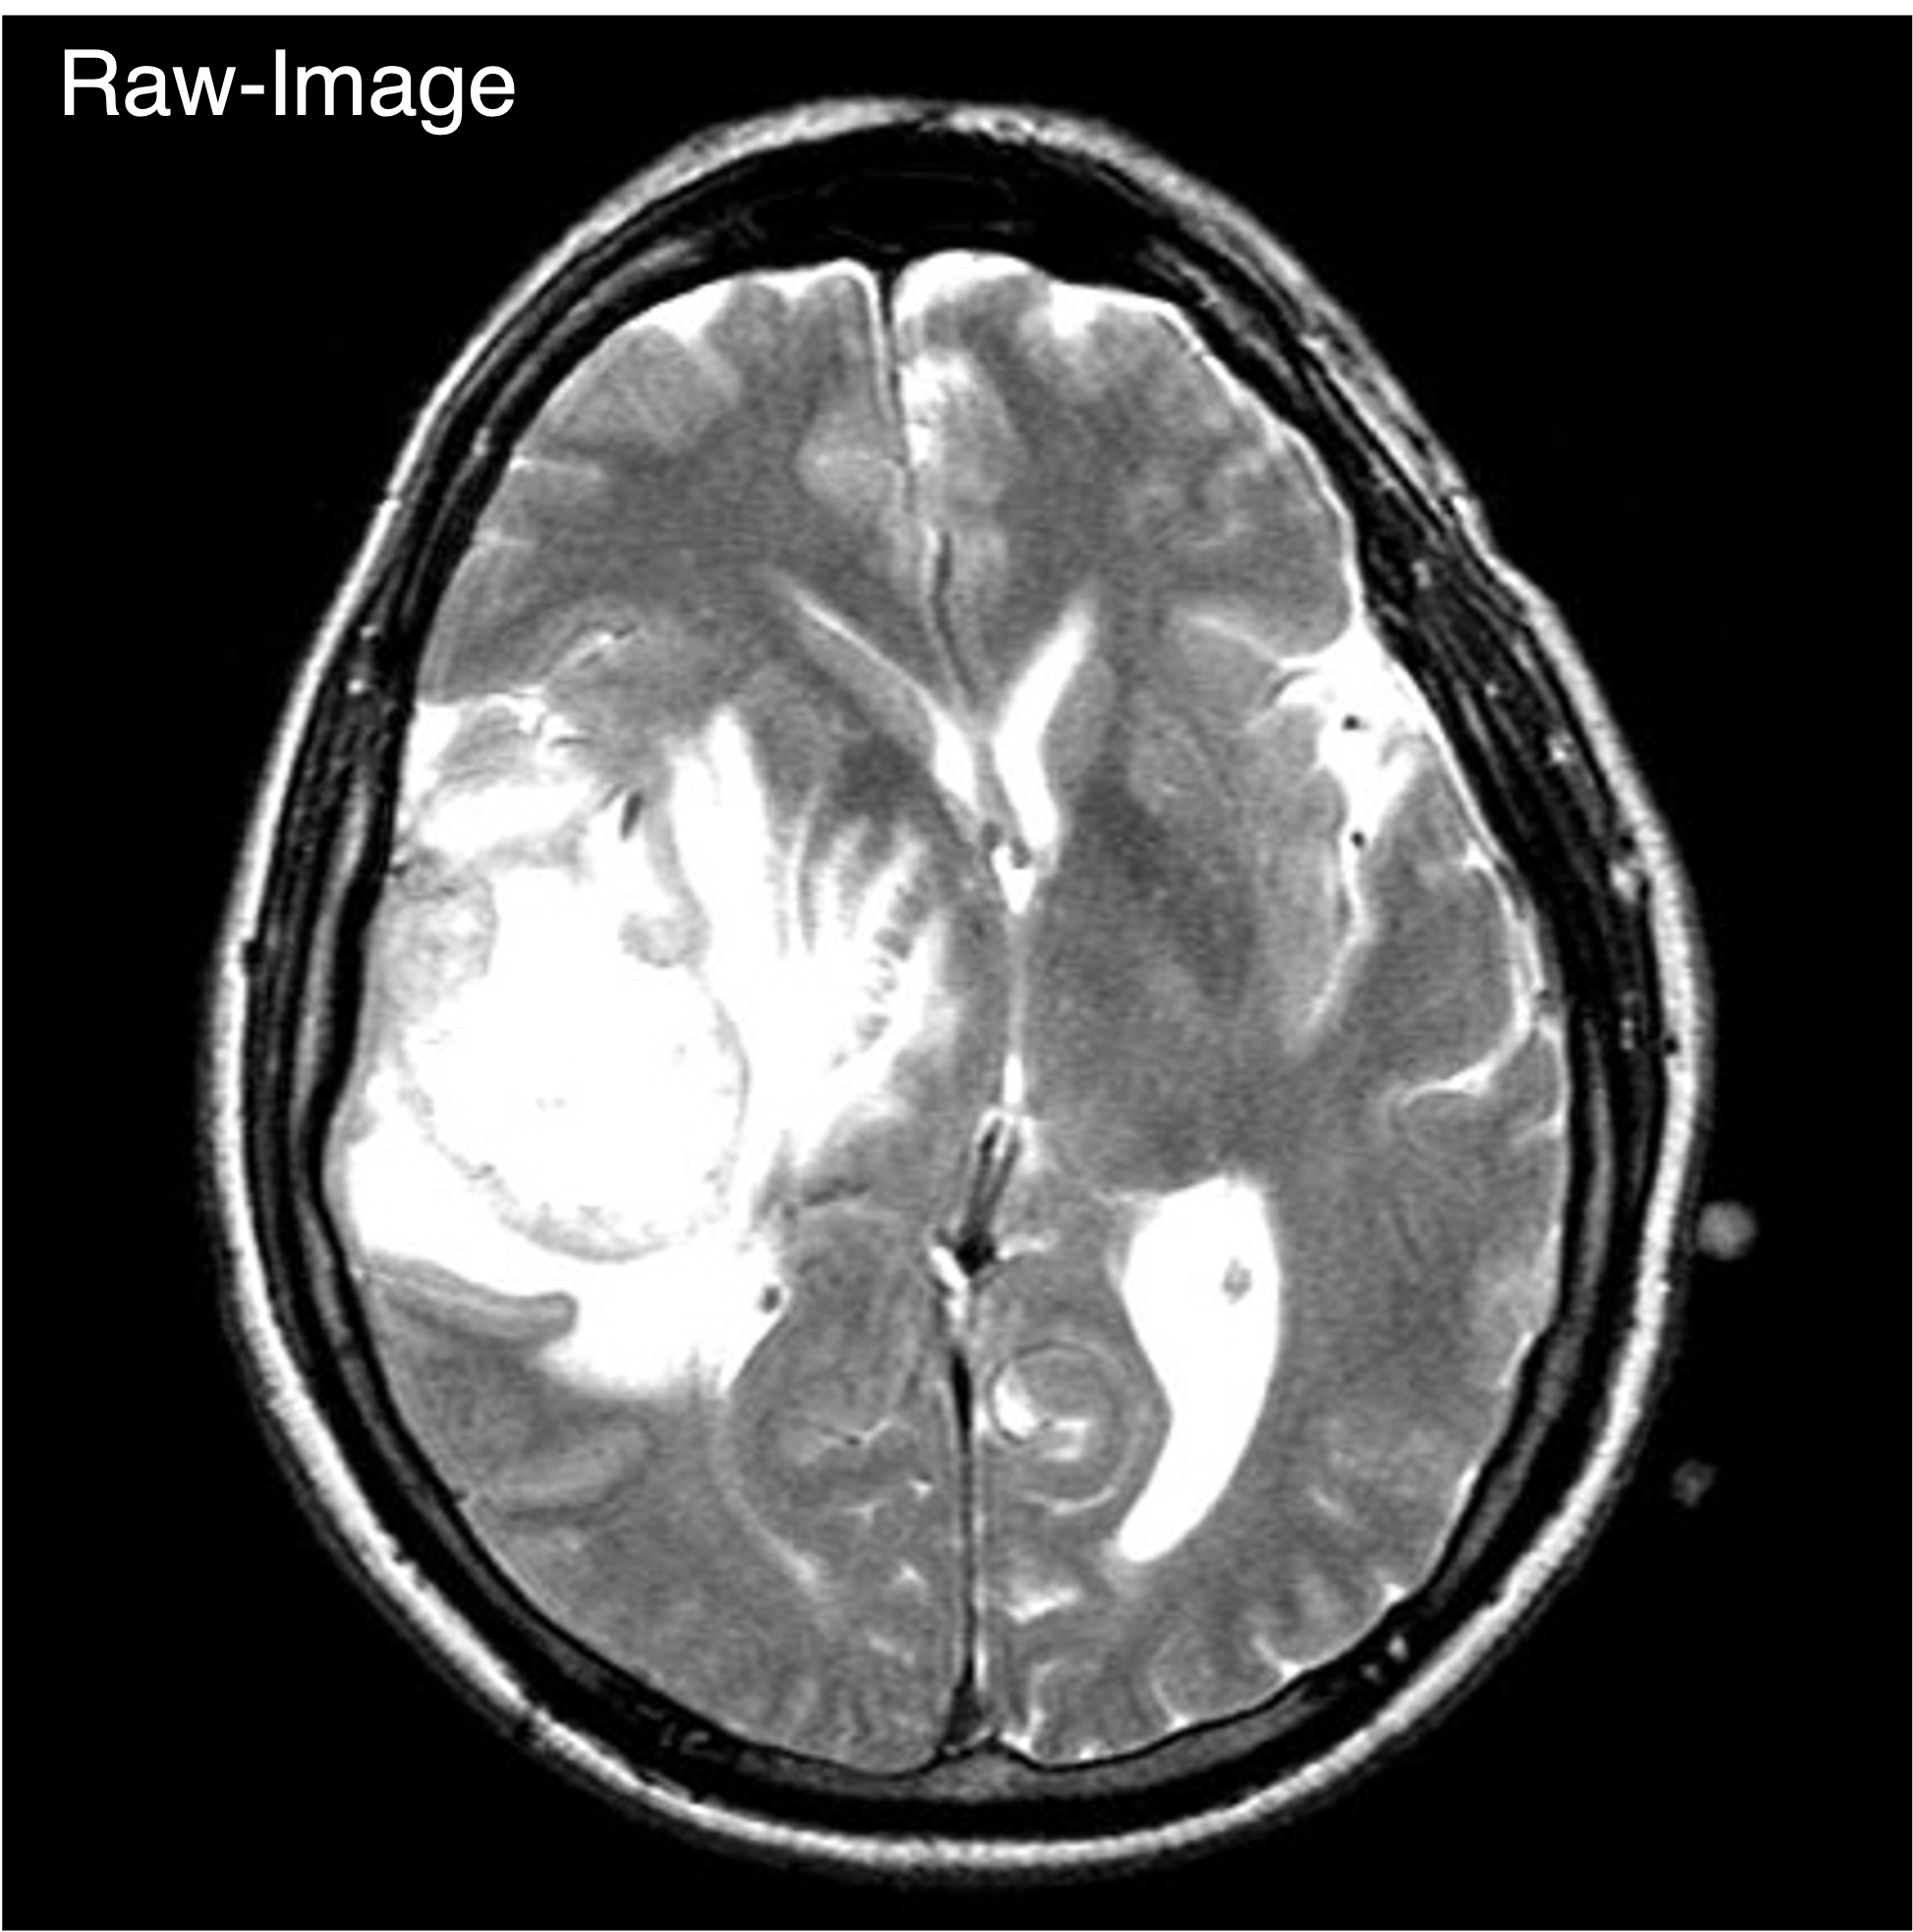

Qualitative Comparison. Comparison results between various state-of-the-art detection methods and the proposed method is shown above. Our method effectively leverages modality context to significantly enhance anomaly localization (red), compared to baseline results (blue). Ground truth bounding boxes are green. For cases where the bounding boxes are small, insets show an enlarged view of the highlighted yellow region.